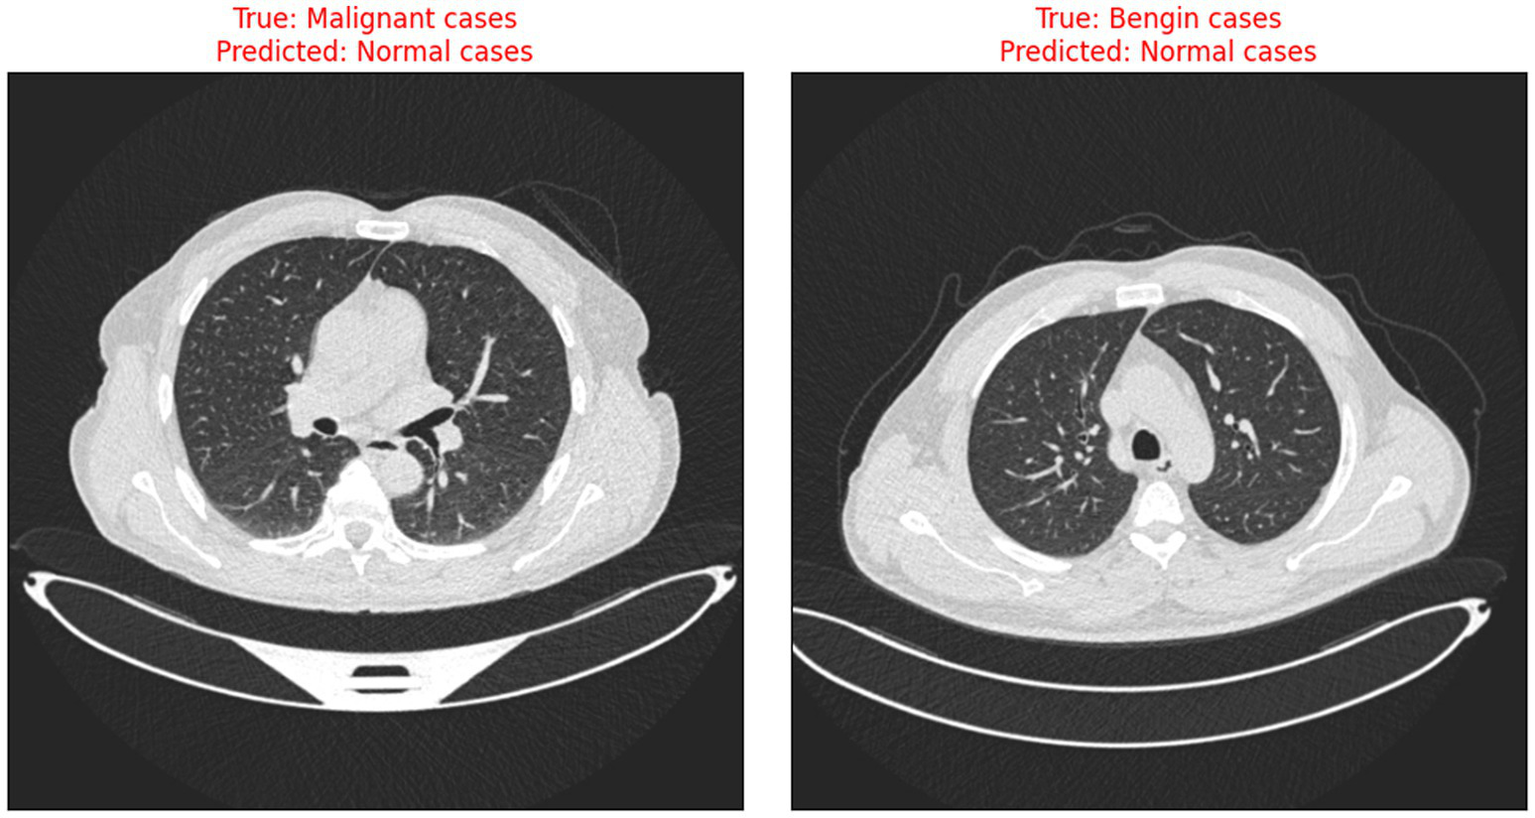

The risks associated with misclassification, particularly false negatives in malignant cases are significant in clinical settings. It is crucial that such tools are used as decision-support systems rather than standalone diagnostic solutions, and that their outputs are always interpreted by qualified clinicians. Transparent reporting of model performance and clear communication of its limitations are essential to minimize patient harm and uphold ethical standards in medical AI. Figure 9 illustrates the instances when the model incorrectly classified benign and malignant cases as normal, thus indicating the need for further improvement in distinguishing between minor differences in CT scan images.

Figure 9

Examples of misclassified CT scans.